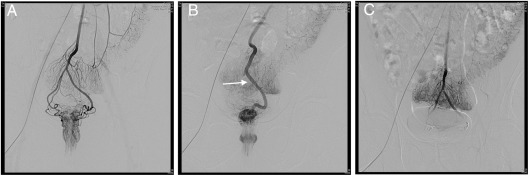

Es un tratamiento moderno, novedoso, mínimamente invasivo, que viene siendo utilizado desde el 2014 para el manejo de las hemorroides, consiste en un procedimiento mínimamente invasivo, guiado por ecografía y rayos X, tambien conocido como cateterismo con el cual se accede a las arterias que irrigan la región ano-rectal para ocluirlas y quitar su aporte a las hemorroides

La mayoría de veces las hemorroides requieren manejo médico y en algunos casos cirugía, sin embargo, existe otra alternativa para el tratamiento que es la llamada EMBOLIZACIÓN, la cual consiste en procedimiento mínimamente invasivo de última generación, con un cateterismo, que se realiza de las arterias hemorroidales o rectales, las cuales se taponan con un material de uso médico, para quitar la irrigación de las hemorroides e inducir su involución. Este procedimiento se realiza de forma ambulatoria con equipos de alta tecnología en una clínica privada de 4 nivel , bajo anestesia local , a través de una pequeña punción(sin cicatrices), de forma más segura que la cirugía, con menor tiempo de recuperación y sin duda alguna mejorando la calidad de vida

La embolización de hemorroides tiene una eficacia entre el 75% Y 95% para el control del sangrado y los síntomas. Con la ventaja que al ser un procedimiento mínimamente invasivo se puede repetir las veces que sea necesario o combinar con otras técnicas como las escleroterapia percutánea.